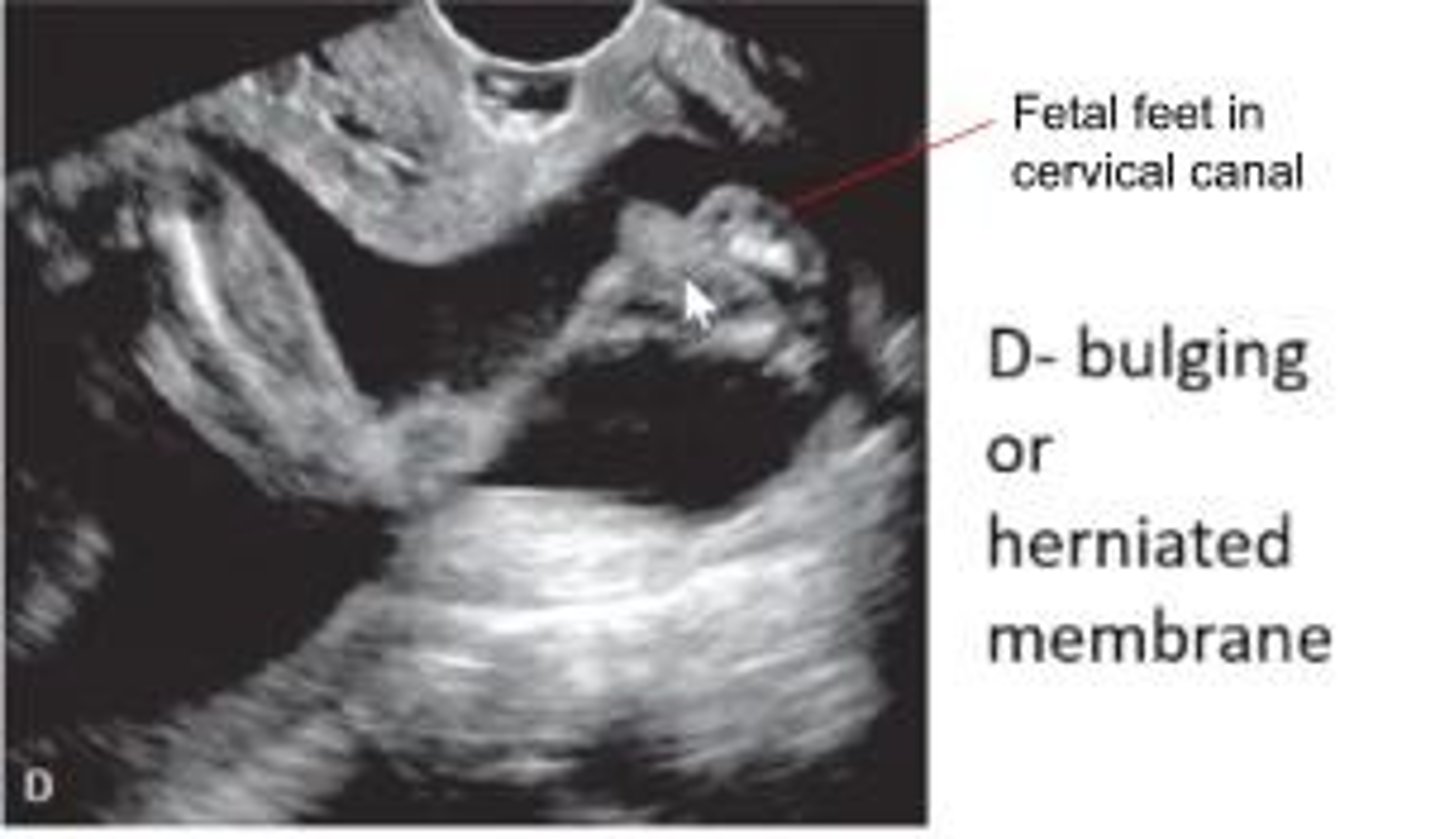

What is a bulging amnion?

Amnion extends into endocervical canal and vagina.

What is a rescue cerclage? When is it performed?

- Performed when cervix dilates over 1-2 cm by physical exam/US

- Push the herniated membranes back into the uterine cavity and close cx w/ rescue stitch

- Performed as a last resort

Which funnel shape has the worst prognosis?

a) Y shape

b) U shape

c) T shape

d) V shape

- Since the anterior and posterior lips of the cx are pushed out of the way, there is a greater chance that fetal parts can be seen in the tunnel